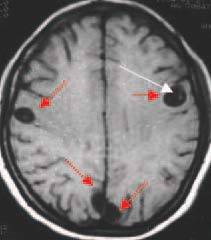

So, when the egg stage is swallowed from dookie or something that got dookie on it, you end up with the tunneling stage of the tapeworm...and that's not even the worst of it. The worst of it is that the tunneling stage of a pork tapeworm is adapted for, you know, a pig. You're not a pig. You're not shaped like a pig and you don't have a pig's biochemistry. In a human body, the poor babies never find anything they recognize as swine muscular tissue and they can end up encysting themselves virtually anywhere in the body by mistake, where they might even die and begin to rot by the way.